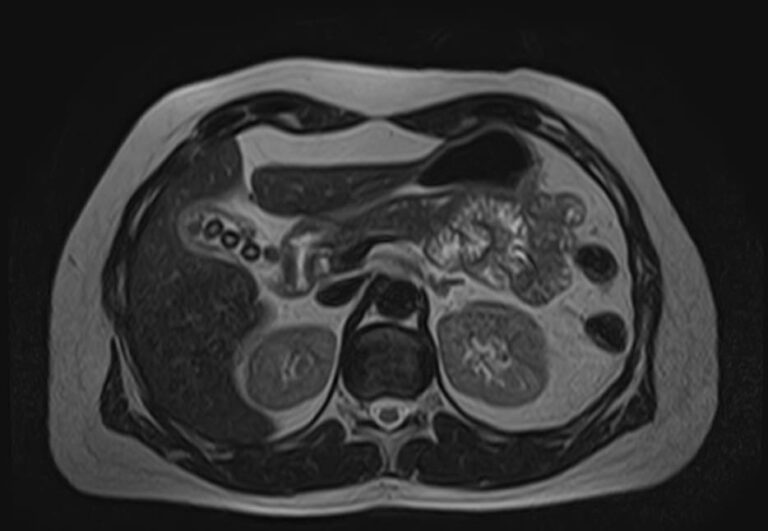

Магнитно-резонансная томография является наиболее точным и информативным методом обследования надпочечников с целью выявления различных заболеваний. Клиника «Доступная медицина» располагает новейшим томографом экспертного уровня TOSHIBA VANTAGE TITAN 1,5 Тесла, который обеспечивает высокую точность и достоверность результатов исследования.

Методика подразумевает послойное сканирование анатомической зоны надпочечников с последующей цифровой обработкой полученных данных для создания трехмерных изображений. Для более детальной визуализации патологических очагов, особенно при подозрении на развитие опухолевых образований, применяется контрастное усиление.

Контрастирование осуществляется путем внутривенного введения препарата, содержащего соли гадолиния. Благодаря способности контрастного вещества фиксироваться в патологических очагах возможно диагностировать опухоли размером от 1 мм. Метод позволяет выявлять опухолевый процесс на начальной стадии, что значительно улучшает прогноз в плане лечения и выздоровления.